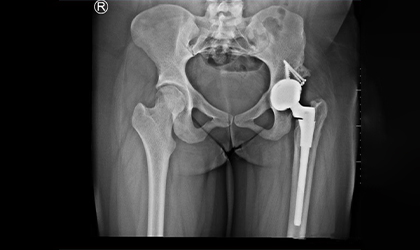

26-year-old woman diagnosed with hip dysplasia characterized by a shallow hip socket. She underwent a left total hip replacement using a specialized prosthesis known as the S-ROM system. Additionally, bone grafting was performed to reconstruct and reinforce the socket walls for better implant support.This is one of the youngest girls I have done a hip replacement in. Did her right hip when she was 13 and the left a year later. She is a blood cancer survivor. She had collapse of both her hips related to chemotherapy (which actually saved her life). She had ceramic bearings. Presently totally symptom free pursuing her higher studies.

Detailed imaging and clinical evaluations revealed developmental dysplasia of the hip. A comprehensive surgical plan was developed, considering the unique anatomy.